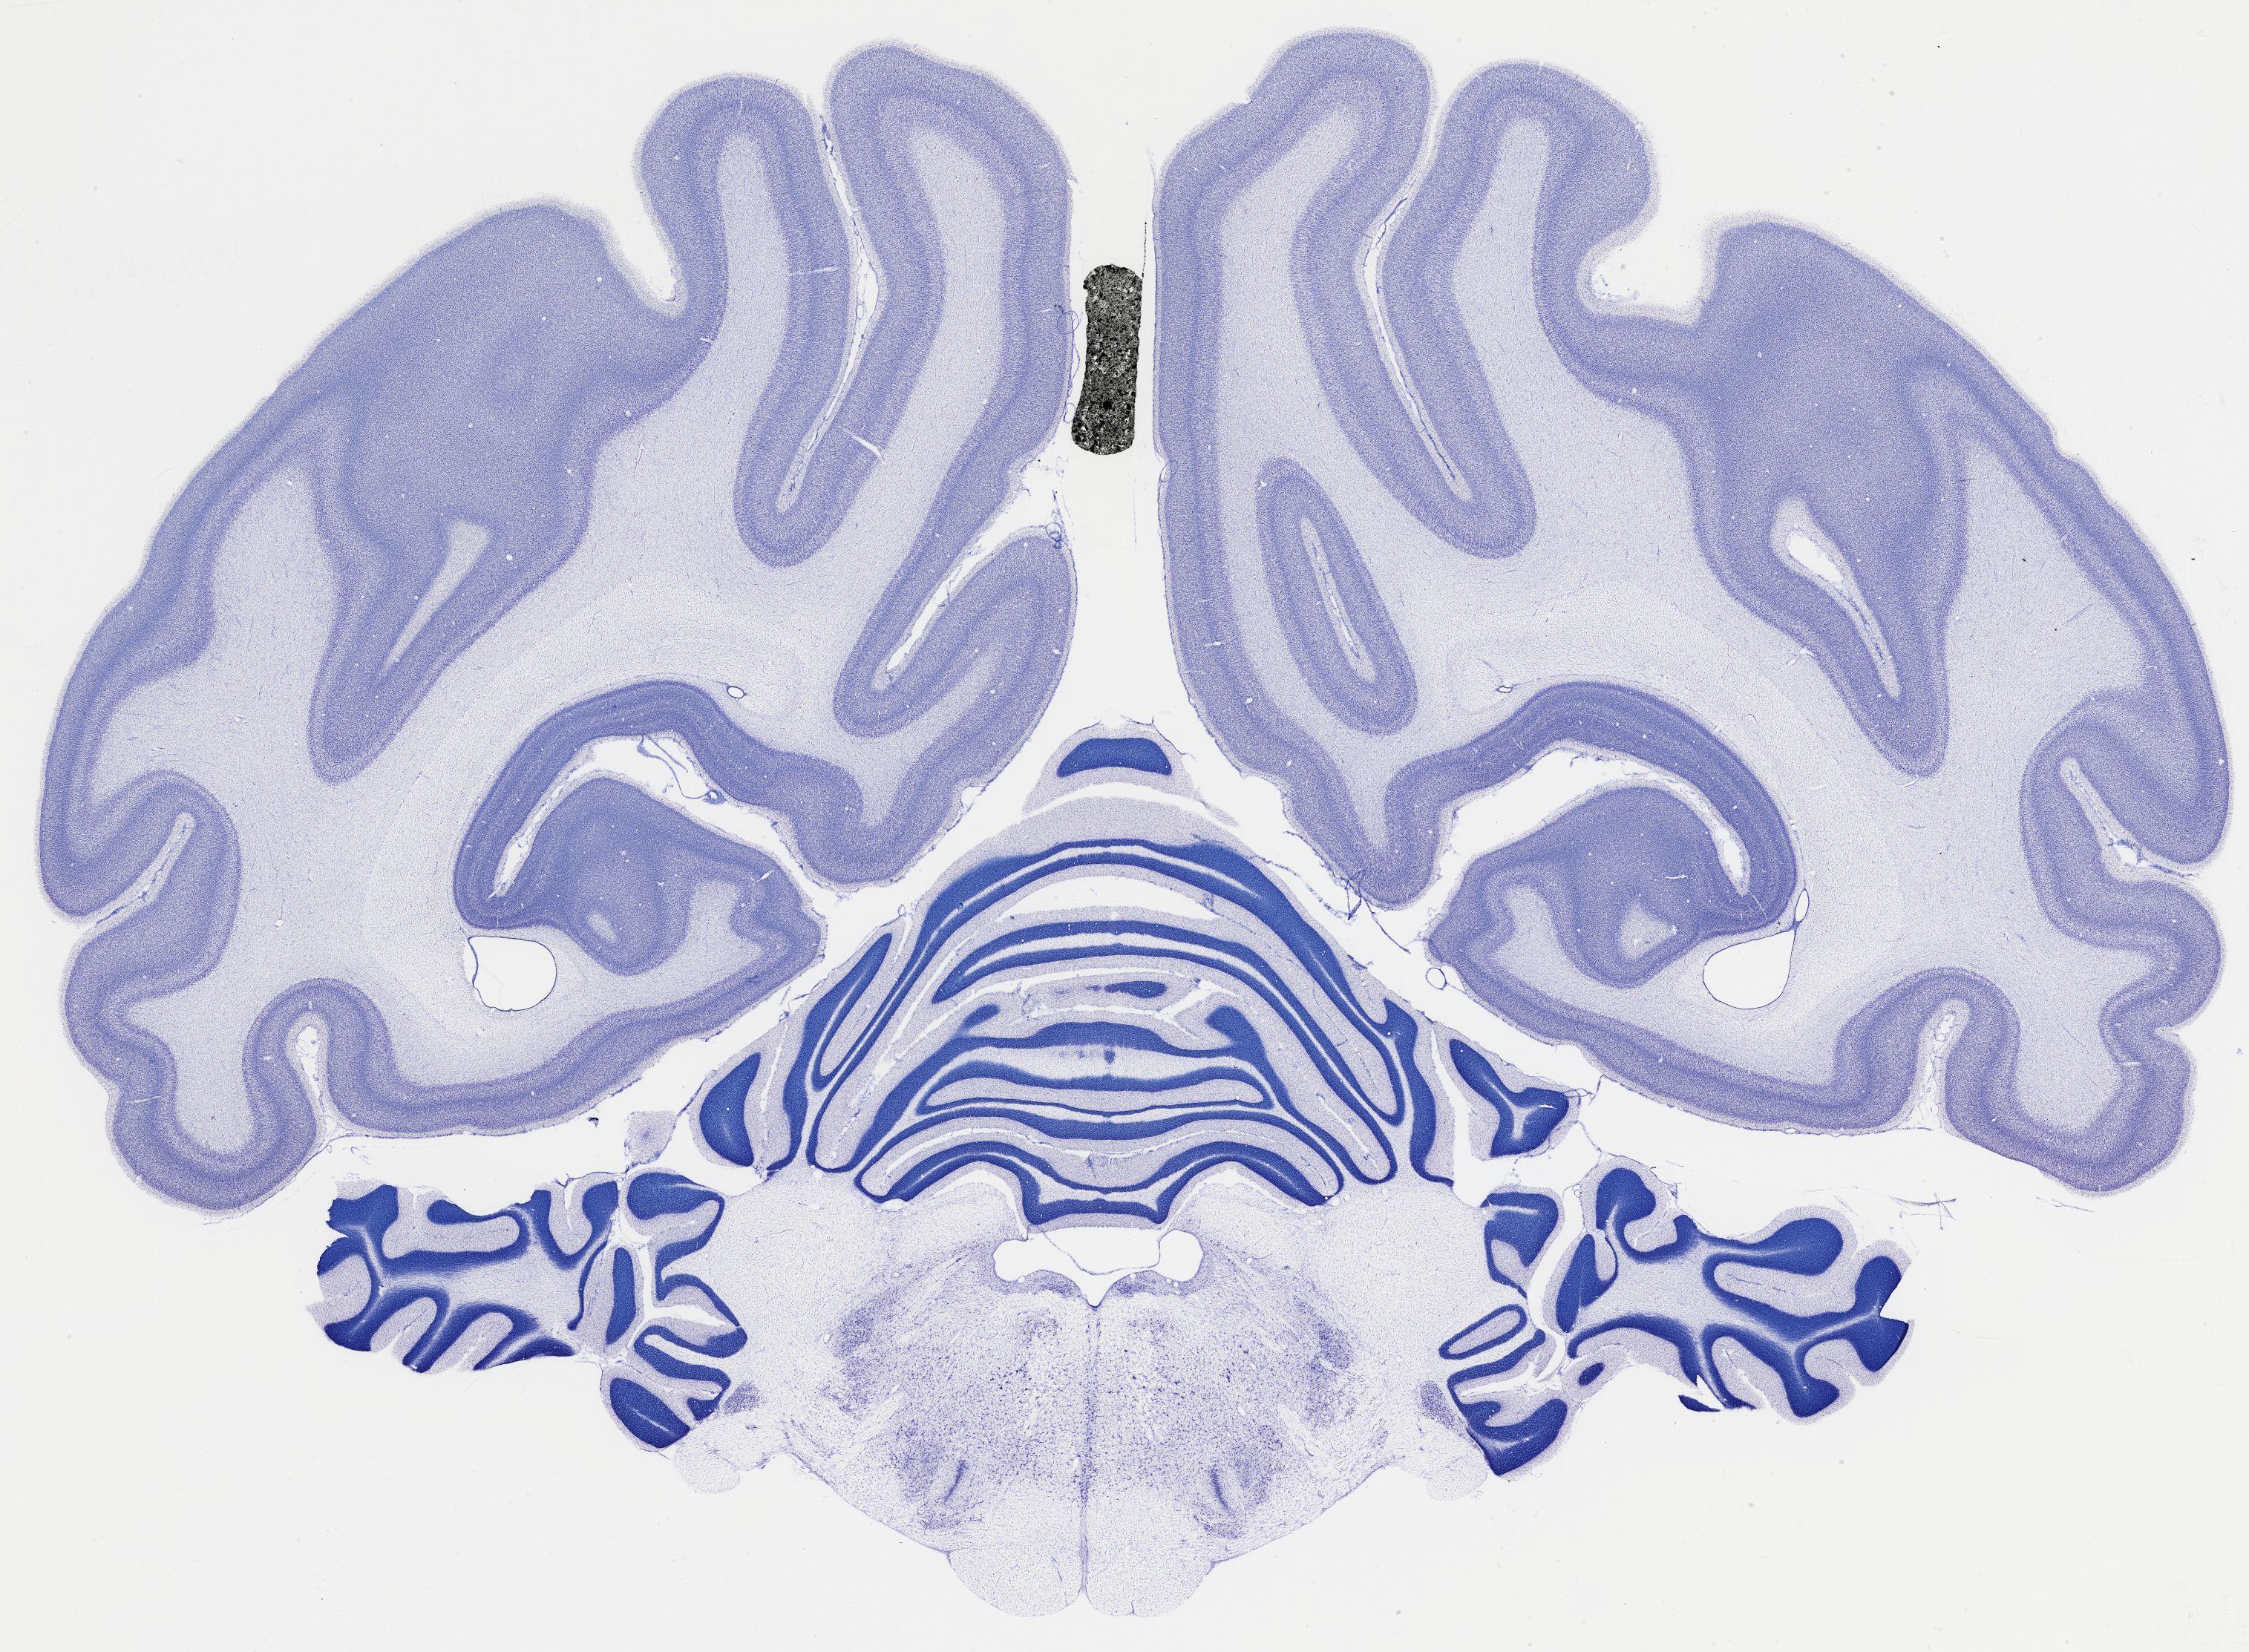

thumbnail

524